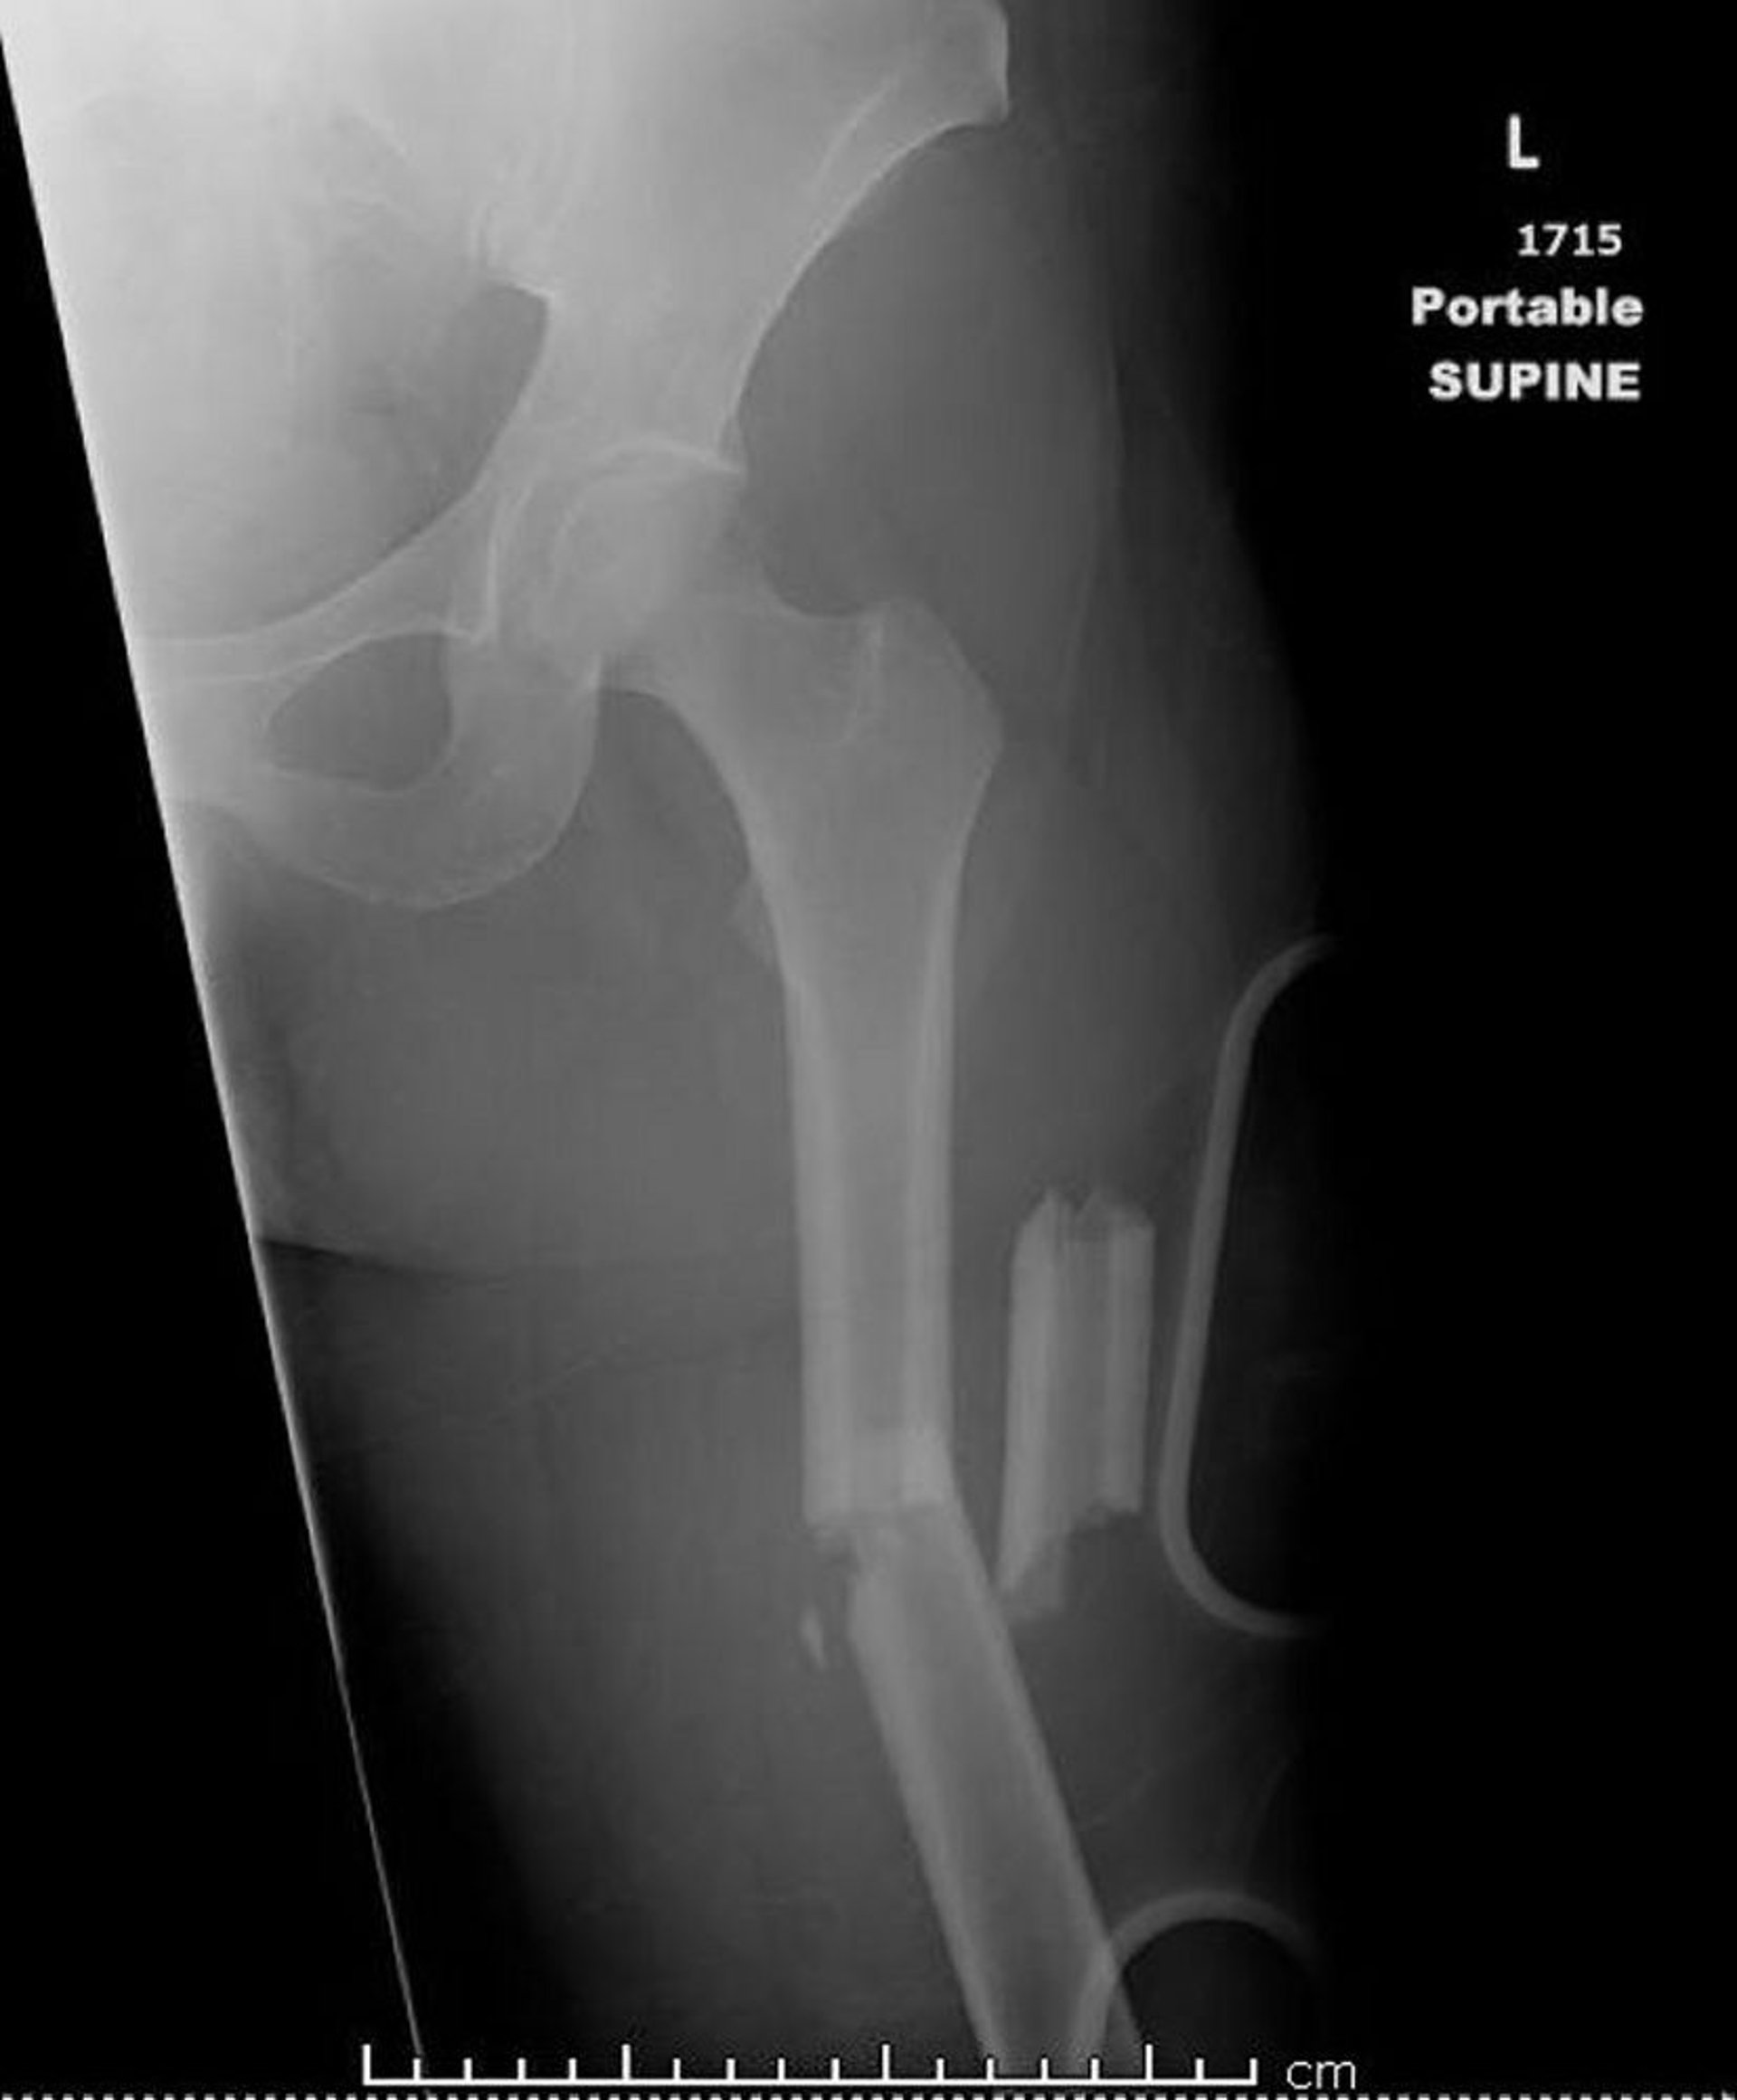

Перелом средней части бедра

На этом изображении показана бедренная кость, которая сломана более чем в двух местах (оскольчатый перелом).

Изображение любезно предоставлено д-ром Даниэллой Кампань (Danielle Campagne).